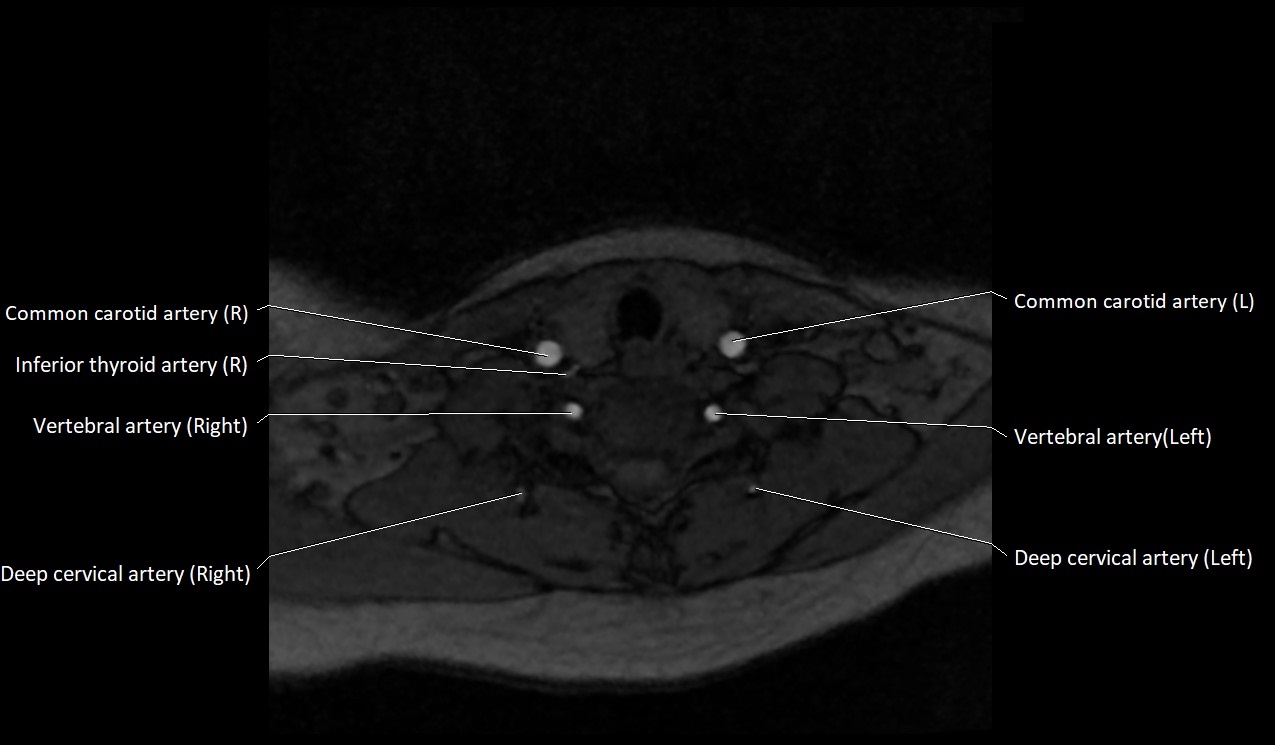

CT image

image